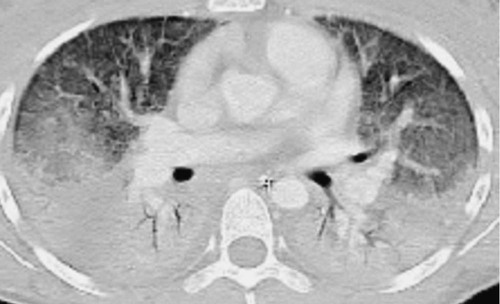

It is important to point out that patients with ARDS may be especially vulnerable to VILI because of the heterogeneous nature of the pulmonary parenchymal injury. On computed tomography scans of the lungs, normal-appearing lung and densely consolidated injured lung are both seen; as a consequence, there are marked regional differences in lung compliance113 (Fig. 100-5). A tidal volume designed to inflate an entire lung would preferentially inflate the normal-appearing areas, potentially leading to overdistention and volutrauma. Patients with ARDS may similarly be more vulnerable to atelectrauma. Although some evidence suggests that normal lungs can tolerate at least short periods of cyclic opening and closing of airways from mechanical ventilation,114 injured lungs, such as in ARDS, would be exposed to much higher shear stresses and would not be expected to fare as well.115